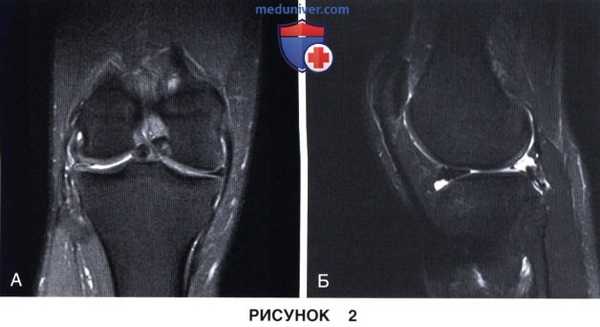

1. Целостность мениска и состояние его периферической зоны (рис. 1 и 2):

• Остатки нативного мениска можно использовать в качестве шаблона для определения размеров необходимого трансплантата мениска